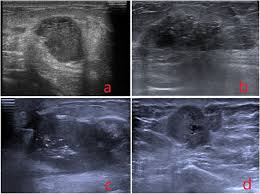

Ultrasound imaging allows better evaluation of the status of the axillary lymph nodes in patients with ibc, an important step in determining extent of disease prior to initiation of chemotherapy. However, a dark spot on your ultrasound doesn't mean that you. It is the most common cause of cancer death in women. in 2005 alone, 519 000 deaths were recorded due to breast cancer. this means that one in every 100 deaths worldwide and almost one in every 15 cancer deaths were due to breast cancer. On ultrasound, a breast cancer tumor is often seen as hypoechoic, has irregular borders, and may appear spiculated. In the table the differences in ultrasound appearances are listed.

Molecular Markers Pathology And Ultrasound Features Of Invasive Breast Cancer Clinical Imaging from els-jbs-prod-cdn.jbs.elsevierhealth.com Sometimes breast cancer can look like a fibroadenoma and fibroadenomas can look like a cancer on ultrasound. What does the doctor look for on a mammogram? cancer.org. You can get dressed straight after the ultrasound. On ultrasound, a breast cancer tumor is often seen as hypoechoic, has irregular borders, and may appear spiculated. When is breast ultrasound used? Benign and malignant characteristics of breast lesions at ultrasound allow the classification as either malignant, intermediate or benign based on work published by stavros et al. Ultrasound characterization of breast masses. indian journal of radiology and imaging. However, a dark spot on your ultrasound doesn't mean that you.

Cysts, tumors, and growths will appear as dark areas on the scan. Breast ultrasound uses sound waves to make a computer picture of the inside of the breast. What does a solid mass look like in an ultrasound breast image? Ultrasound of triple negative breast cancer. This is a network of thin tubes (vessels) and nodes that carry a clear fluid called lymph around the body. A breast ultrasound is most often done to find out if a problem found by a mammogram or physical exam of the breast may be a cyst filled with fluid or a solid tumor. Solid lesions can be a little brighter or darker than the surrounding tissue, and the way to evaluate these on ultrasound is to look closely at the margins or the outer edges of the nodule. In the table the differences in ultrasound appearances are listed. Ibc is a rapidly progressive, aggressive form of breast cancer associated with a low overall survival rate. On the flip side, there are benign (not cancerous) breast changes which can mimic breast cancer as well. What does breast cancer look like on a mammogram? American cancer society, 9 oct 2017. Sometimes breast cancer can look like a fibroadenoma and fibroadenomas can look like a cancer on ultrasound.

Any area that does not look like normal tissue is a possible cause for concern. Below are images of dcis on breast ultrasound. Ultrasound is not used on its own as a screening test for breast cancer. Ultrasound (us) shows an irregular, hypoechoic (dark gray) spiculated mass (arrow), highly suspicious for cancer. This is because it may miss some early signs of cancer.